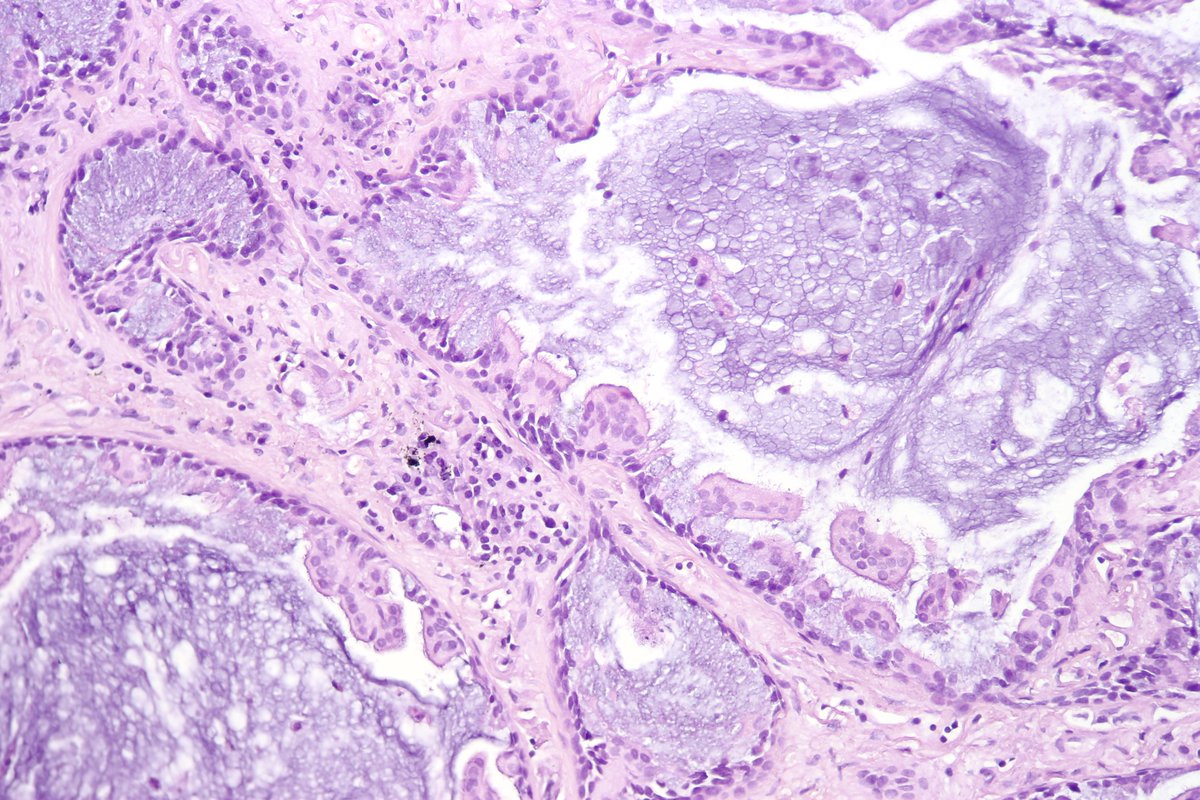

Type B2 Thymoma showing prominent large epithelial cells admixed with numerous lymphocytes. #pathology #PulmPath